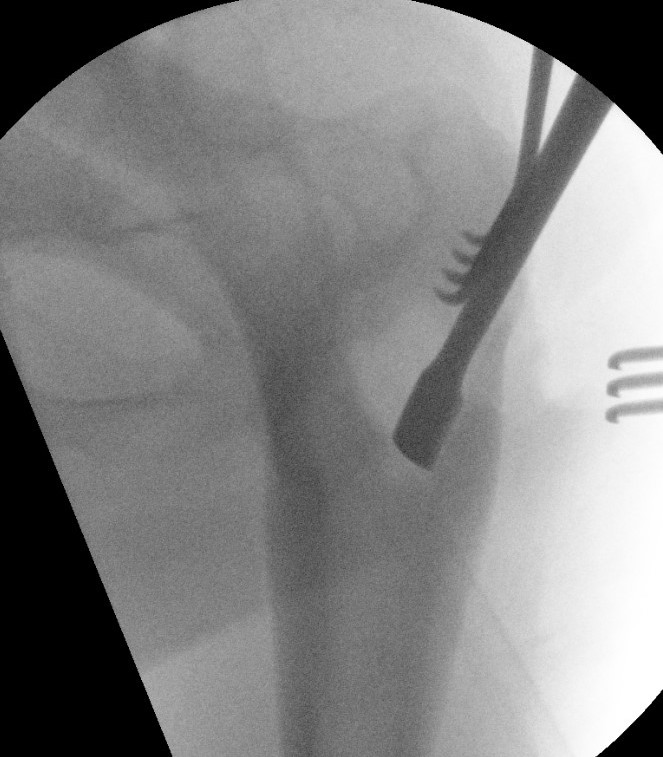

Radiofrequency ablation

- clinical success rate 90 - 95%

Arrigoni et al Int J Hyperthermia 2018

- 11 patients with spinal OB treated with RF ablation

- complete pain relief in all patients

- no additional treatment required